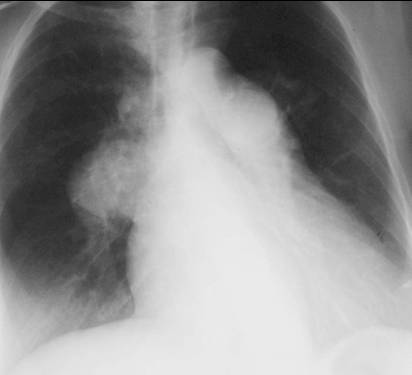

The peripheral pulmonary vasculature is normal whereas the central vasculature is prominent.